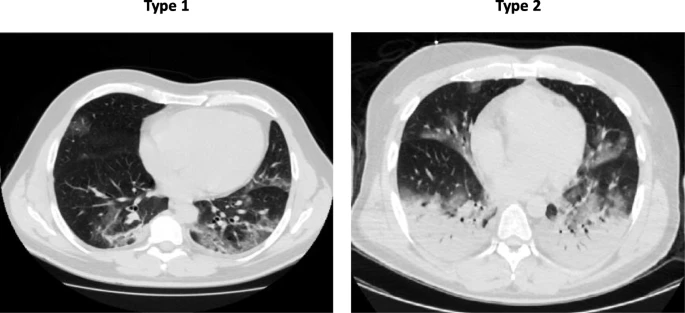

In these patients, severe hypoxemia is associated with respiratory system compliance > 50 ml/cmH2O. The lung’s gas volume is high, the recruitability is minimal, and the hypoxemia is likely due to the loss of hypoxic pulmonary vasoconstriction and impaired regulation of pulmonary blood flow. Therefore, severe hypoxemia is primarily due to ventilation/perfusion (VA/Q) mismatch. High PEEP and prone positioning do not improve oxygenation through recruitment of collapsed areas, but redistribute pulmonary perfusion, improving the VA/Q relationship. Lung CT scans in those patients confirm that there are no significant areas to recruit, but the right-to-left venous admixture is typically around 50%.